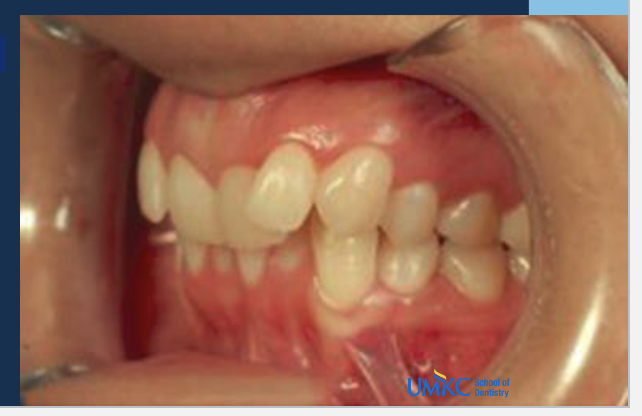

Q

A

class 2